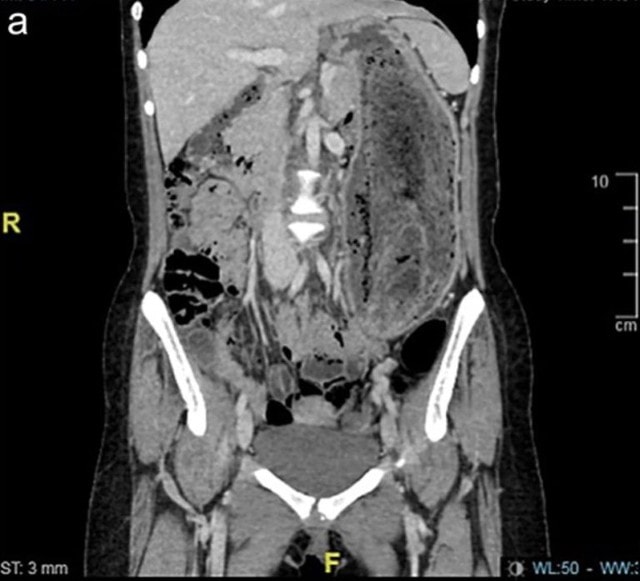

Trong khi tất cả các xét nghiệm trong phòng thí nghiệm đều bình thường, kết quả chụp CT xác nhận rằng búi tóc khổng lồ đã kéo dài từ dạ dày đến tá tràng.

Do kích thước của khối tóc, việc loại bỏ bằng phương pháp nội soi là không thể nên nữ bệnh nhân đã phải trải qua phẫu thuật mở dưới gây mê toàn thân.